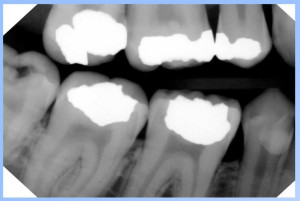

SuniRay2

-CMOS Sensor

-No Idea on Line Pairs, It is not advertised.

The image quality is pretty good and they claim greater durability.